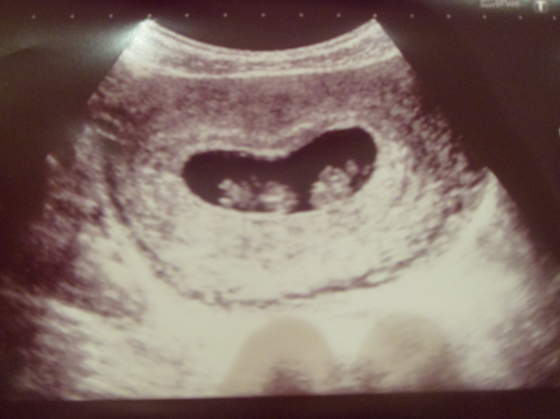

. Miałam dokładne usg w 28tc, teraz to nawet nie wiem jak jest. U mnie dziewczynka jest też tak jakby gł.ębej położona i czuję jej ruchy znaczni słabiej, ale jeśli lekarz mówi że jest ok to tak pewnie jest :-)